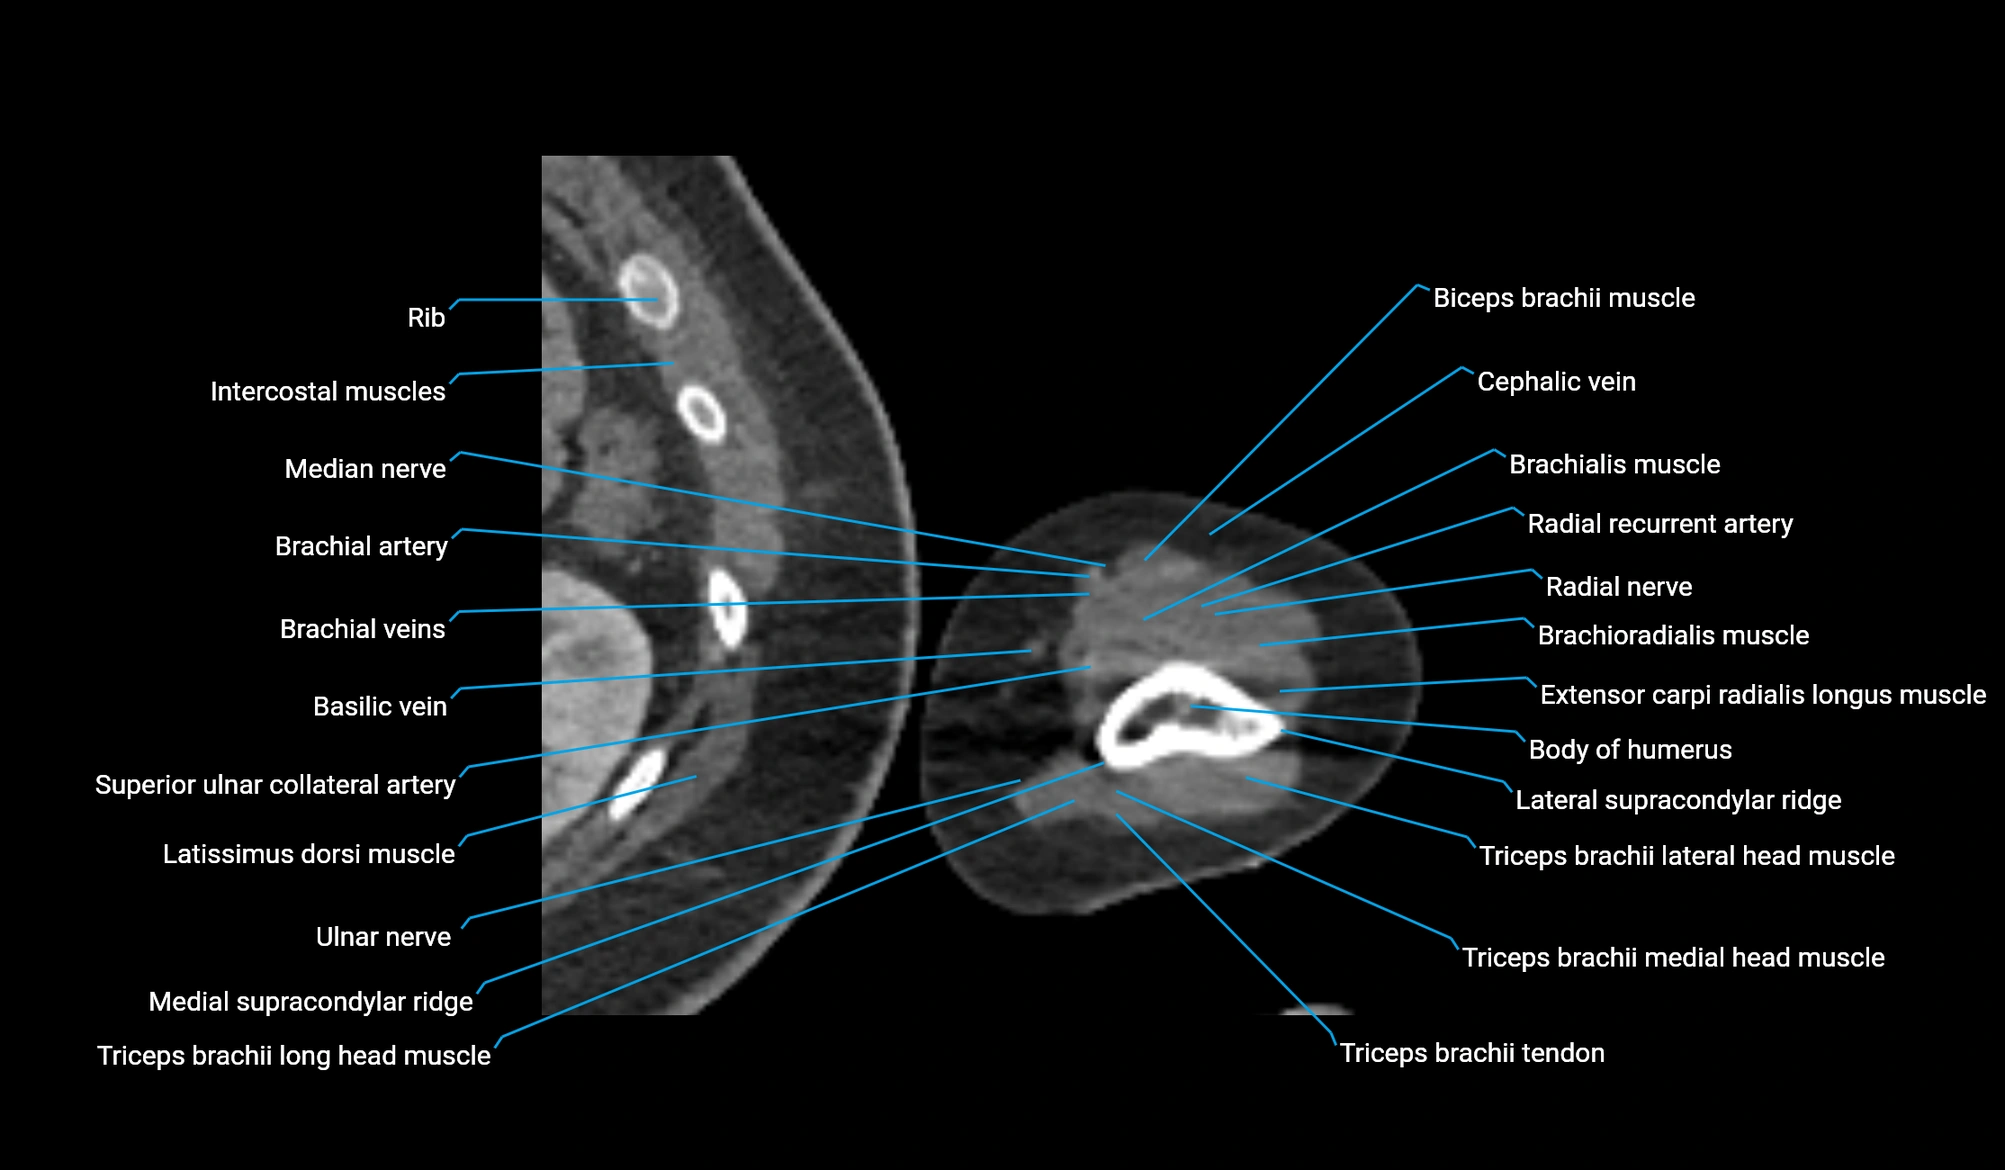

- Body of humerus

- Brachialis muscle

- Brachioradialis muscle

- Cephalic vein

- Deep brachial artery

- Extensor carpi radialis longus muscle

- Lateral head of triceps brachii muscle

- Lateral supracondylar ridge

- Long head of triceps brachii muscle

- Medial head of triceps brachii muscle

- Medial supracondylar ridge

- Median nerve

- Radial nerve

- Radial recurrent artery

- Superior ulnar collateral artery

- Triceps brachii tendon